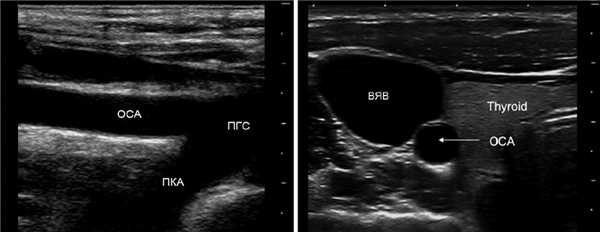

Для исследования ПГС датчик располагают в яременой вырезке, луч направляют вправо. ПГС делится на правую ПКА и ОСА. Устье левой ОСА и ПКА слишком глубоко, чтобы видеть.

ПКА I сегмент исследуют над грудино-ключичным сочленением, II сегмент — над ключицей направляют луч вниз, III сегмент — под ключицей.

Для исследования ОСА датчик располагают вдоль наружного или внутреннего края кивательной мышцы. ОСА оценивают на всем протяжении от устья до бифуркации.

У основания шеи кнутри от ОСА щитовидная железа, кнаружи — внутренняя яремная вена. Под давлением датчика ВЯВ сжимается, а ОСА нет.

На уровне бифуркации ВСА шире НСА; расположена кнаружи и кзади от НСА, выше перемещается кнутри; не имеет ветвей на шее.